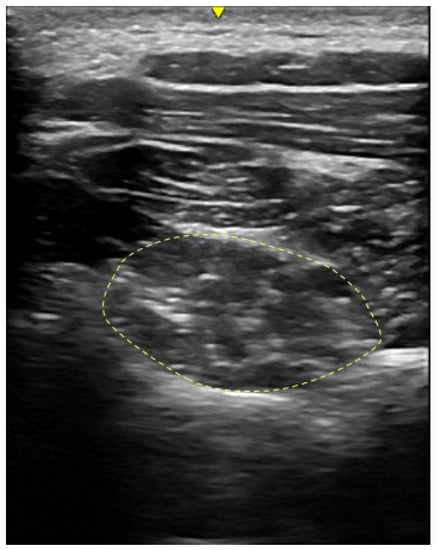

2.3.3. Morphological Characteristics of Deep Neck Muscles